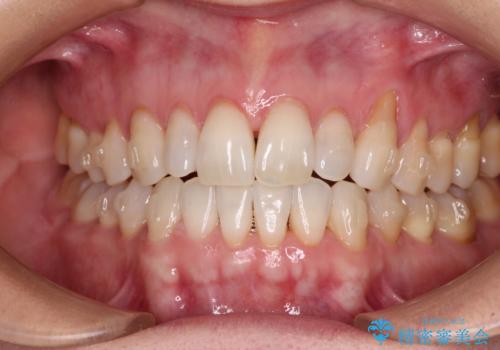

- 前歯の上下スペースによる食べにくさを気にして来院された患者様です。

インビザラインにより上下の前歯の隙間を閉じていくこととしました。

舌の突出癖があると上下前歯にスペースが開くため、矯正治療を機会に舌癖を改善するトレーニングを行ってもらい、矯正治療後の後戻りを防止するように指導しています。